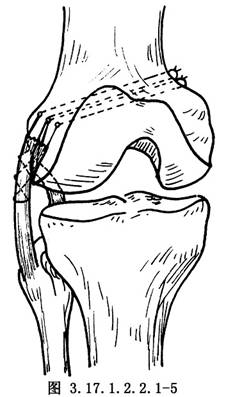

如半月板和交叉韌帶有損傷,儘可能予以修補,然後再自後側開始修補外側結構。①如有後外側關節囊撕脫,將其牽到脛骨關節面下方,用圓針引絲線穿過脛骨關節面下的鑽孔,由前到後縫合固定在脛骨上(圖3.17.1.2.2.1-4)。固定前將脛骨附着部的骨表面弄毛糙,或用骨刀做一新鮮骨創面,以保證後外側關節囊的固定。②有膕肌腱撕裂者,按損傷類型採用不同的方法。股骨附着部的膕肌腱撕裂,常伴有外側副韌帶自股骨上撕脫,可採用Bunnell縫合,通過股骨的鑽孔,捆紮在股骨內上髁的骨面上(圖3.17.1.2.2.1-5)。膕肌腱本身撕裂,將兩端用Bunnell縫合(圖3.17.1.2.2.1-6)。撕裂在肌肉內或肌腱連接部,用Bunnell縫合通過脛骨前外側近端Gerdg結節的骨孔,將肌腱附着到脛骨的後面(圖3.17.1.2.2.1-7)。③修補外側副韌帶。對外側副韌帶的撕裂先明確撕裂的部位,對股骨附着部的撕脫可採用U形釘、螺釘固定,或將斷端用Bunnell縫合,通過股骨的鑽孔捆紮在股骨內上髁上。外側副韌帶從腓骨頂點撕裂則伴有股二頭肌腱、弓狀韌帶及腓側副韌帶附着點的複合撕脫,應一併修復,在腓骨頭穿孔,粗線縫合固定。伴有骨片撕脫,可用1枚螺釘或交叉克氏針固定骨片(圖3.17.1.2.2.1-8)。如爲韌帶本身的撕裂,找出兩斷端拉緊後屈膝30°位,用不吸收的絲線對端或重疊縫合(圖3.17.1.2.2.1-9)。並將外側緣向前推進,縫合在外側正中關節囊的後緣和外側副韌帶的後緣。還可應用股二頭肌腱、腓腸肌腱和髂脛束加強修補。